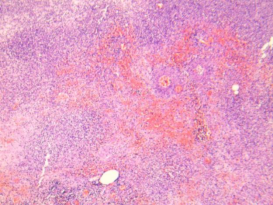

坏疽性阑尾炎

常为化脓性阑尾炎继续发展的结果,由于系膜炎症使阑尾静脉血栓形成,从而引起阑尾广泛出血梗死,阑尾各层广泛出血坏死和急性炎细胞浸润。肌层出血坏死严重者可引起穿孔。

黏膜及肌层坏死,浆膜下大量中性粒

细胞,伴坏死、出血